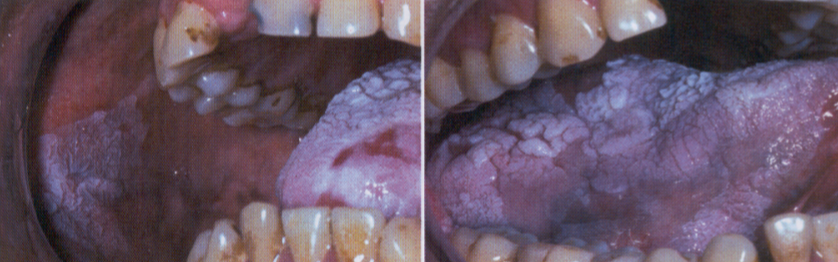

PVL (proliferative verrucous leukoplakia)